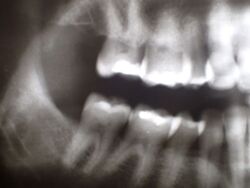

In diesem Zusammenhang wurde heute noch ein Übersichtsröntgenbild erstellt, dass einen ganz typischen, aber häufig nicht bekannten Befund mit sich bringt.

Obwohl die Patientin erkennbar eine gute Mundhygiene beteibt, zeigt sich im gesamten Oberkiefer und hier vor allem im Bereich der Backenzähne ein ausgeprägte und altersuntypisch weit voran geschrittener Knochenabbau.

Das Typische an diesen Zuständen besteht darin, dass der Knochen im Unterkiefer weitgehend normal erscheint, was bene gerade dafür spricht, dass es sich um kein mundhygienebedingtes Problem des Kieferknochenabbaus handelt.

Sollte über die Funktionsdiagnostik hinaus in diesem Fall eine Funktionstherapie zustande kommen, wäre deren Ziel nicht nur die Beseitigung/Linderung der bekannten funktoinellen Beschwerden, sondern darüber hinaus der Stopp des anhaltenden alveolären Knochenabbaus.